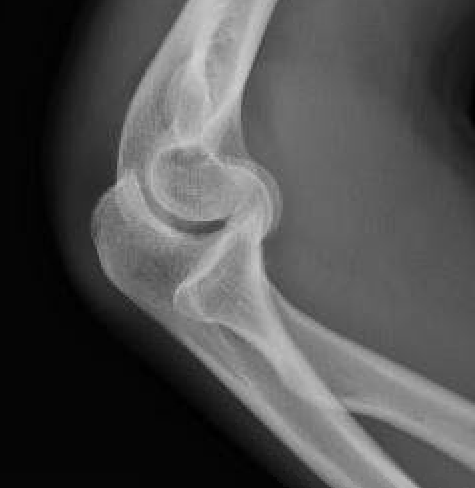

Capitellum fracture with radial head dislocation due to LCL injury